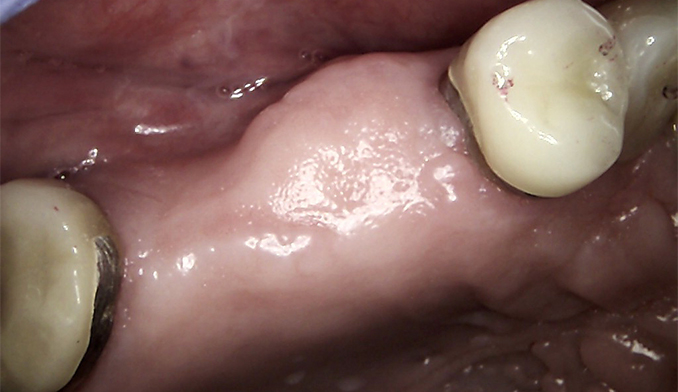

Molar Extraction, Bone Grafting, and Implant Placement

The patient’s lower right molar was severely damaged and could not be saved. After removing the tooth, we performed bone grafting to preserve the bone structure, ensuring a strong foundation for future treatment. Four months later, after proper healing, a dental implant was placed to restore function and maintain jaw health.